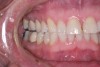

(12.) A patient presented with advanced generalized wear of her anterior teeth, and was displeased with their overall appearance because of their color and wear.

Figure 12

A patient presented with advanced generalized wear of her anterior teeth (Figure 10 and Figure 11). She was displeased with their overall appearance because of their color and wear (Figure 12). A complete examination was performed, revealing instability in her temporomandibular lateral poles bilaterally, sore muscles of mastication, advanced wear, a CR/MIP discrepancy, and loss of her anterior guidance due to the wear. Although the topic is beyond the scope of this article, the patient was also screened for possible sleep apnea. This included an evaluation of the Mallampati score, previous sleep therapy evaluation or treatment, snoring history, an evaluation of her neck size, her weight status, and the presence of the tonsils and their size. In every case, if this clinician suspects airway obstruction to be playing a role in tooth wear issues, the patient is referred to a sleep physician. The patient in this case displayed few apnea risk factors, and the patient’s anterior wear facets fit together like a “lock and key” pattern seen in parafunctional activity. Splint therapy was initiated to stabilize the joints and muscles. A repeatable CR position was verified through load testing. At this point diagnostic models, photographs, a CR bite record, and a facebow were taken and recorded.